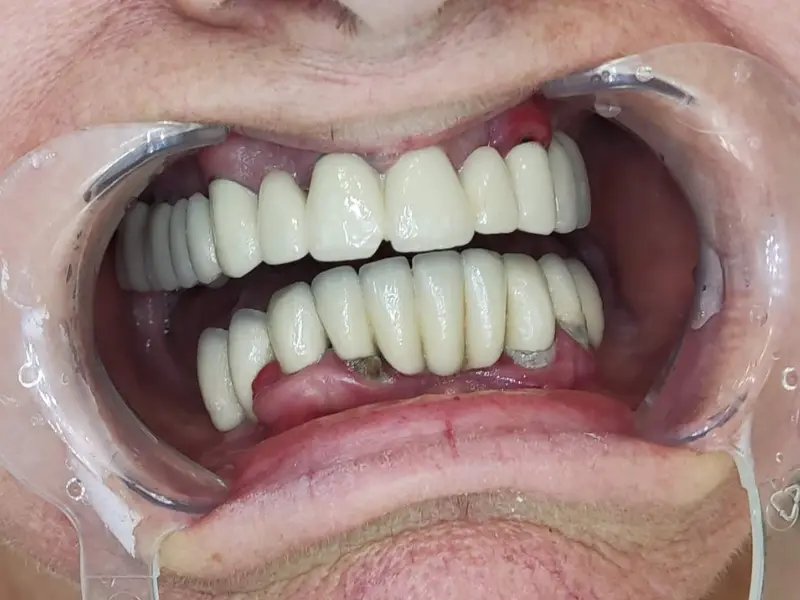

A smile after the procedure

We placed two zygomatic implants and 4 Nobel biocare implants in Milanka's upper jaw, thus using the all on 6 method. We placed 4 Nobel biocare implants in the lower jaw using the all on 4 method. We made a hybrid acrylic bridge in both jaws.